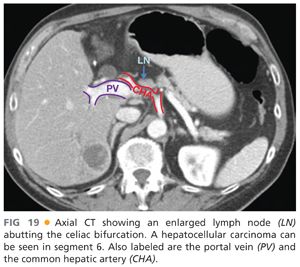

Surgical Anatomy Of The Liver | Abdominal Key

Surgical Anatomy of the Liver | Abdominal Key abdominalkey.com